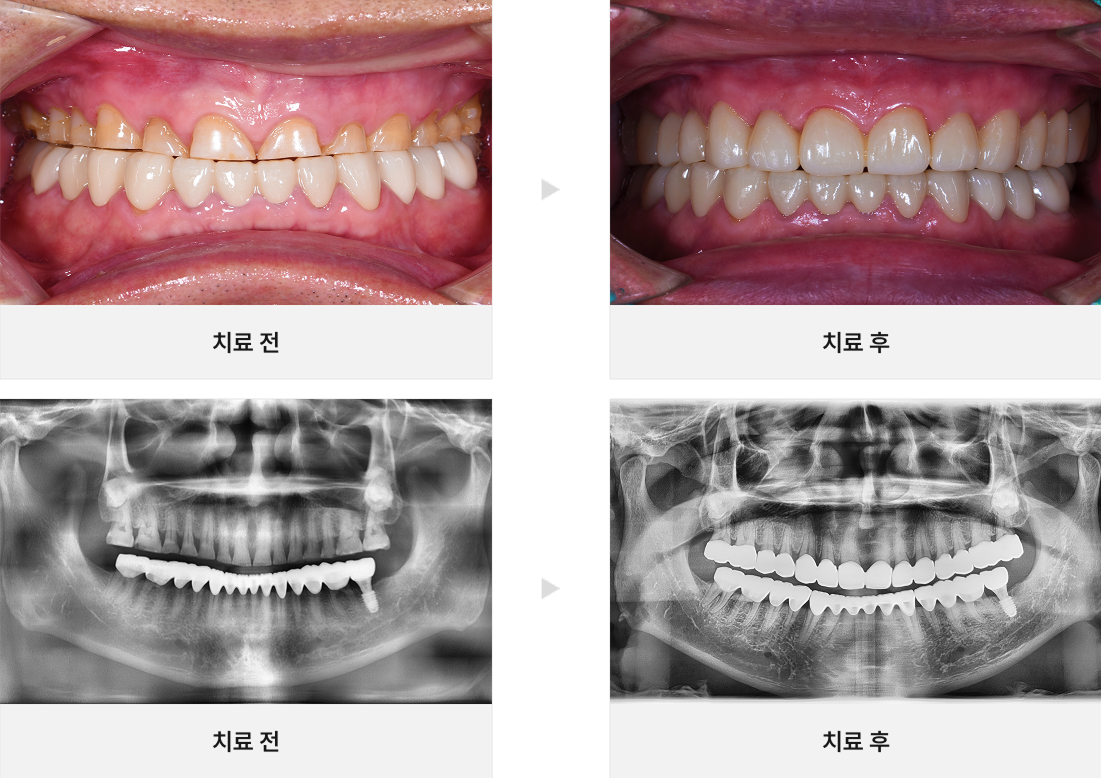

CASE.02

심한마모 치아 살리기